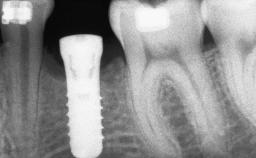

Shell Technique for Horizontal and Vertical Maxillary Bone Augmentation in a Partially Edentulous Patient with Aggressive Periodontal Disease

A 46-year-old woman was referred for treatment whose main complaints were mobility of her fixed partial dentures (right maxilla and left mandible) and periodontal bleeding during function. She also reported having taken systemic antibiotics to treat recurrent swelling in the area of the upper left molars. The patient had not seen a dentist for at least 2 years. She did not smoke and had no history of major systemic disease other than two minor orthopedic procedures some years back. The first-visit examination revealed poor plaque control, tooth mobility, periodontal disease, and a residual dentition widely associated with deep periodontal pockets.

# of Implants 3

Type of Implants One-Piece

Placement Protocol Early or late implant placement